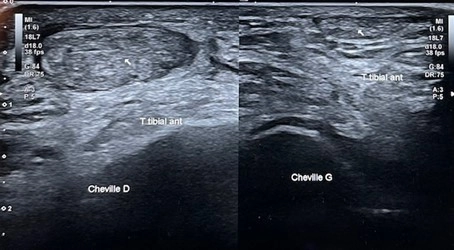

Echographie de la face antérieure de la cheville

24/12/2025